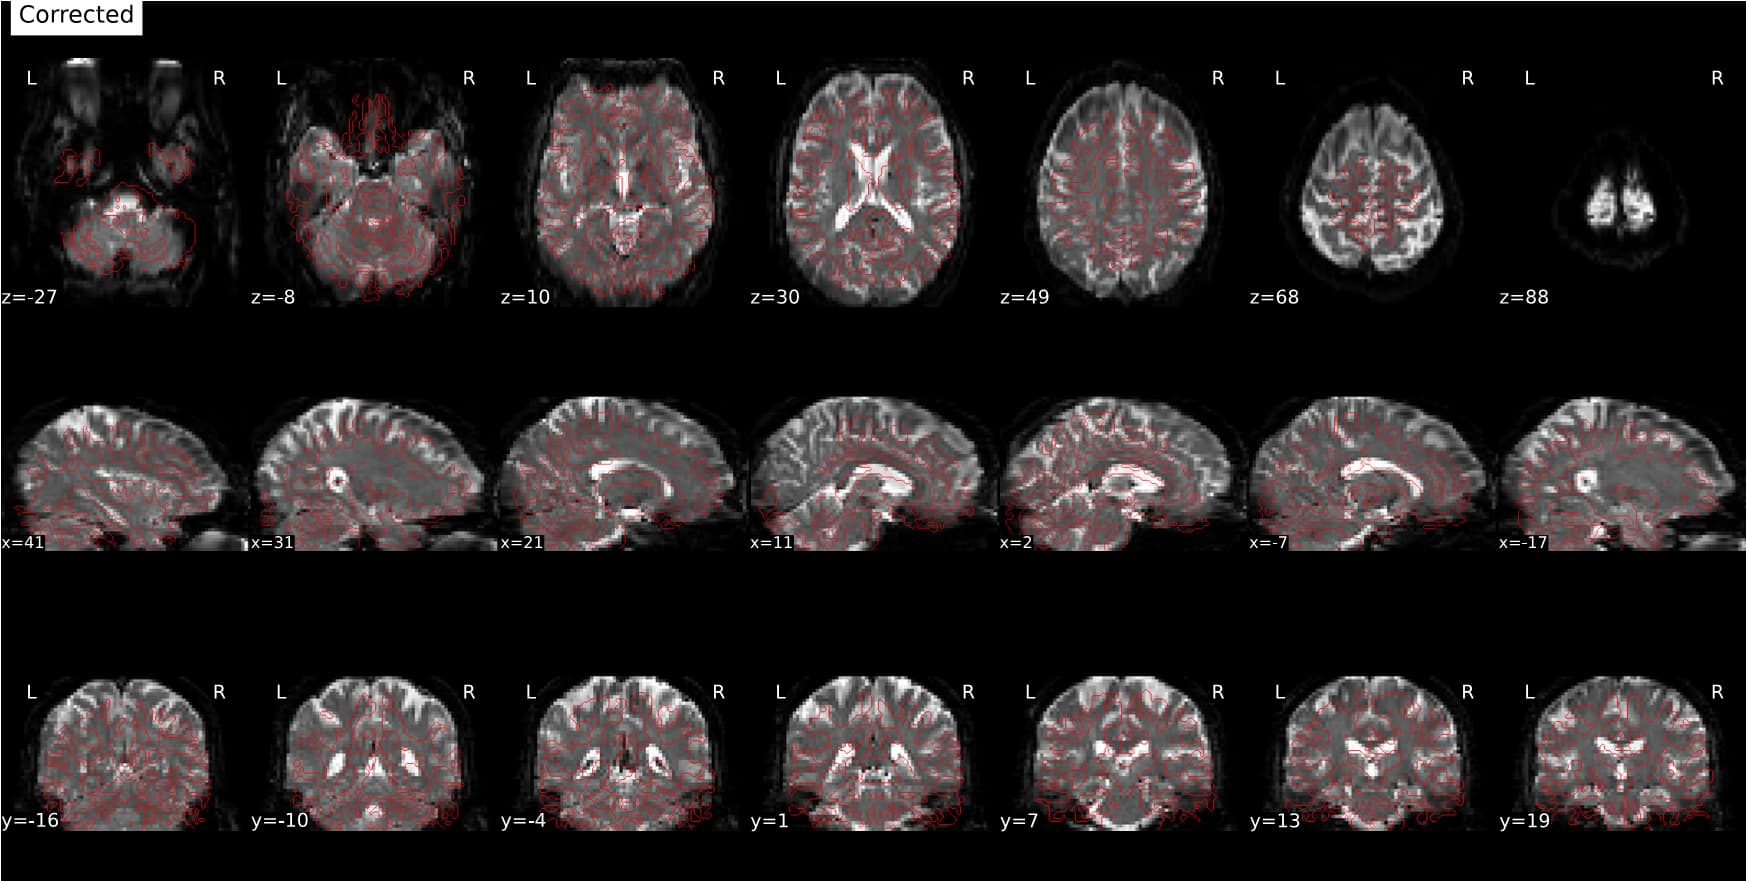

Feed FMRIPREP with the native BOLD image and give in the

fmap/folder:BOLD_s_3D.nii.gzandBOLD_d_3D_smooth.nii.gzimages as being the blip-up and blip-down images to be used with the PEPOLAR method. The PEPOLAR method is callingtopup, as does SynBOLD-DISCO, but I am not sure if SDCFlows (used by FMRIPREP for SDC) would understand how to fill correctly the acquisition parameters file fortopupin that case. -

fmap/folder: the fieldmap in Hz and undistorded magnitude image generated by topup run by SYNB0-DISCO. In that case FMRIPREP would use the Direct B0 mapping method for SDC. That could work! To be tested.